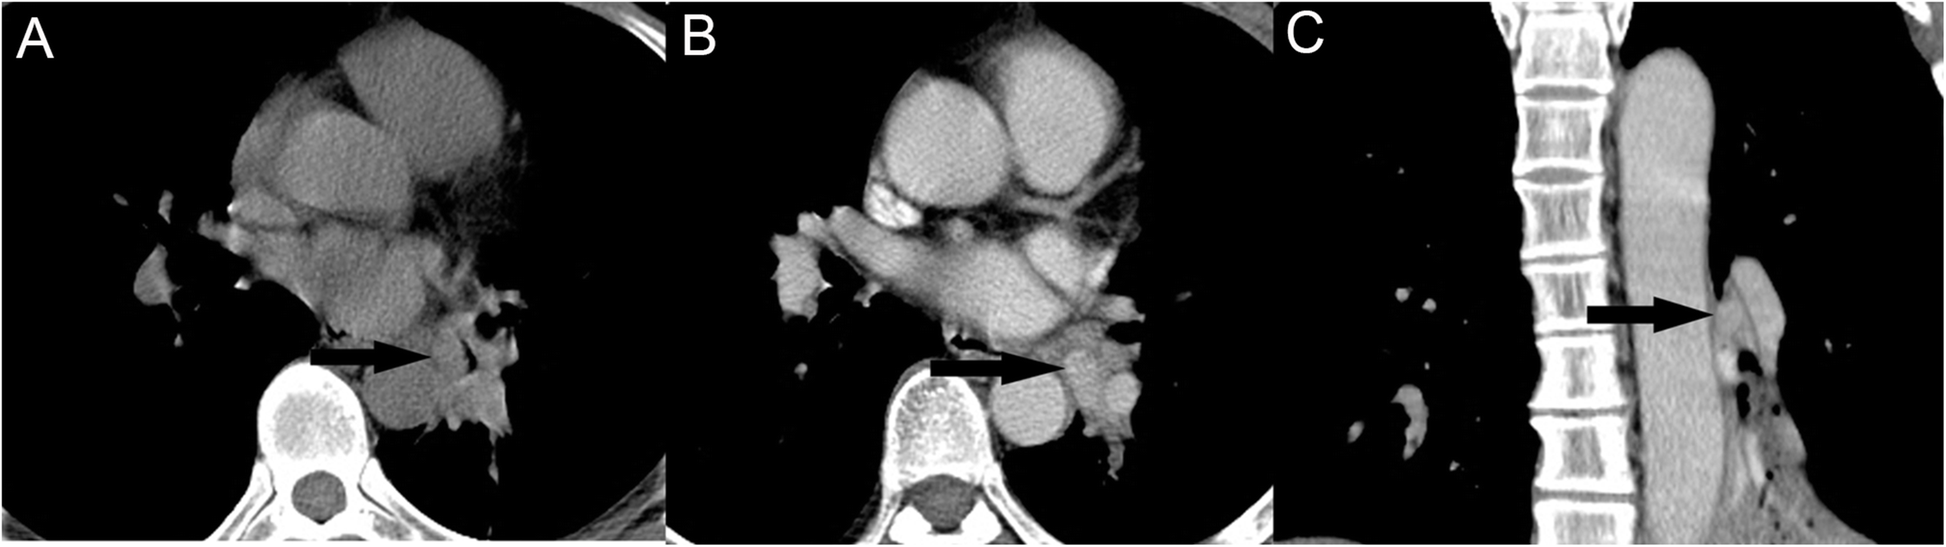

Fig. 1

A PMEC with regular shape and well-defined margin with hilar type. Axial non-contrast CT image (a) shows a isodense mass (arrows) in left inferior lobar bronchus. Contrast-enhanced CT image (b, c) shows tumor with marked enhancement without necrosis (arrows)